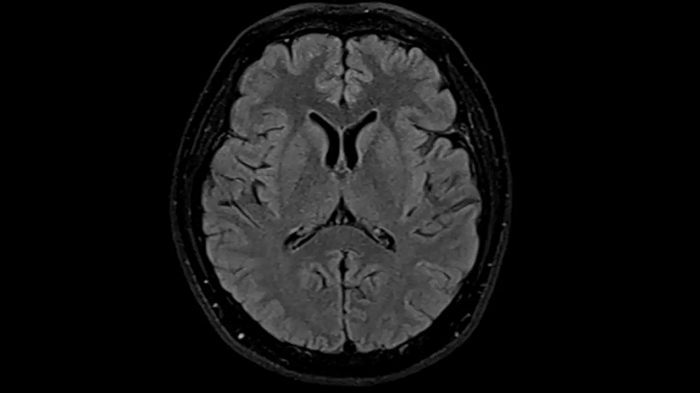

T2 TSE Dark Fluid with Deep Resolve

To produce high-resolution images, Deep Resolve, the Al-powered image reconstruction technology gets benefits from intelligent denoising and neural networks.

Deep Resolve Gain & Sharp

0.4 x 0.4 x 5.0 mm2

TA 4:32 min

MAC-ID: 7aaaa0195. Image Credit: Siemens Healthineers